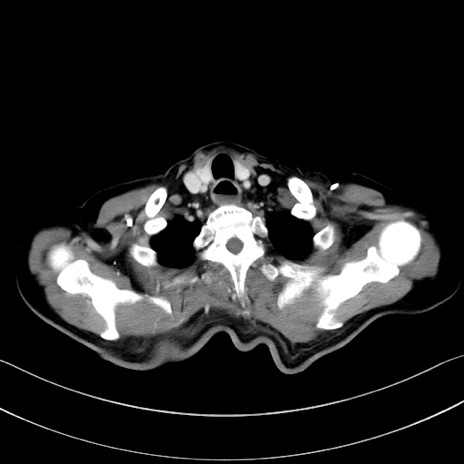

症例28(横断像)

【症例】60歳代男性

【主訴】嘔吐

【現病歴】胃癌にて胃全摘後。食思不振が悪化し、夜中に嘔吐することがある。

【既往歴】胃癌、胃全摘、脾摘、胆摘後

【データ】WBC 5900、CRP 10.56